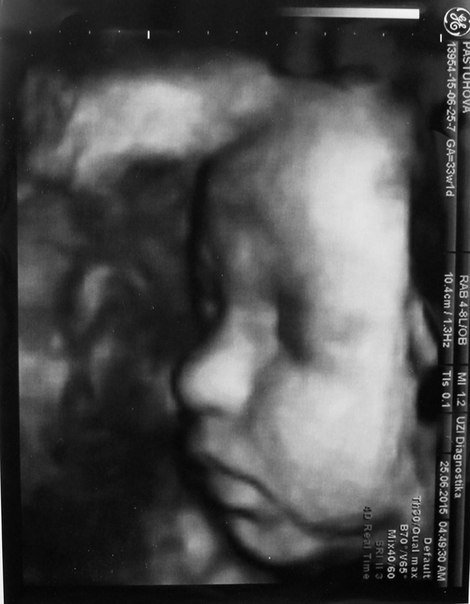

Красавица Алиса, рост 52 см, вес 2740, 8/8 по Апгар